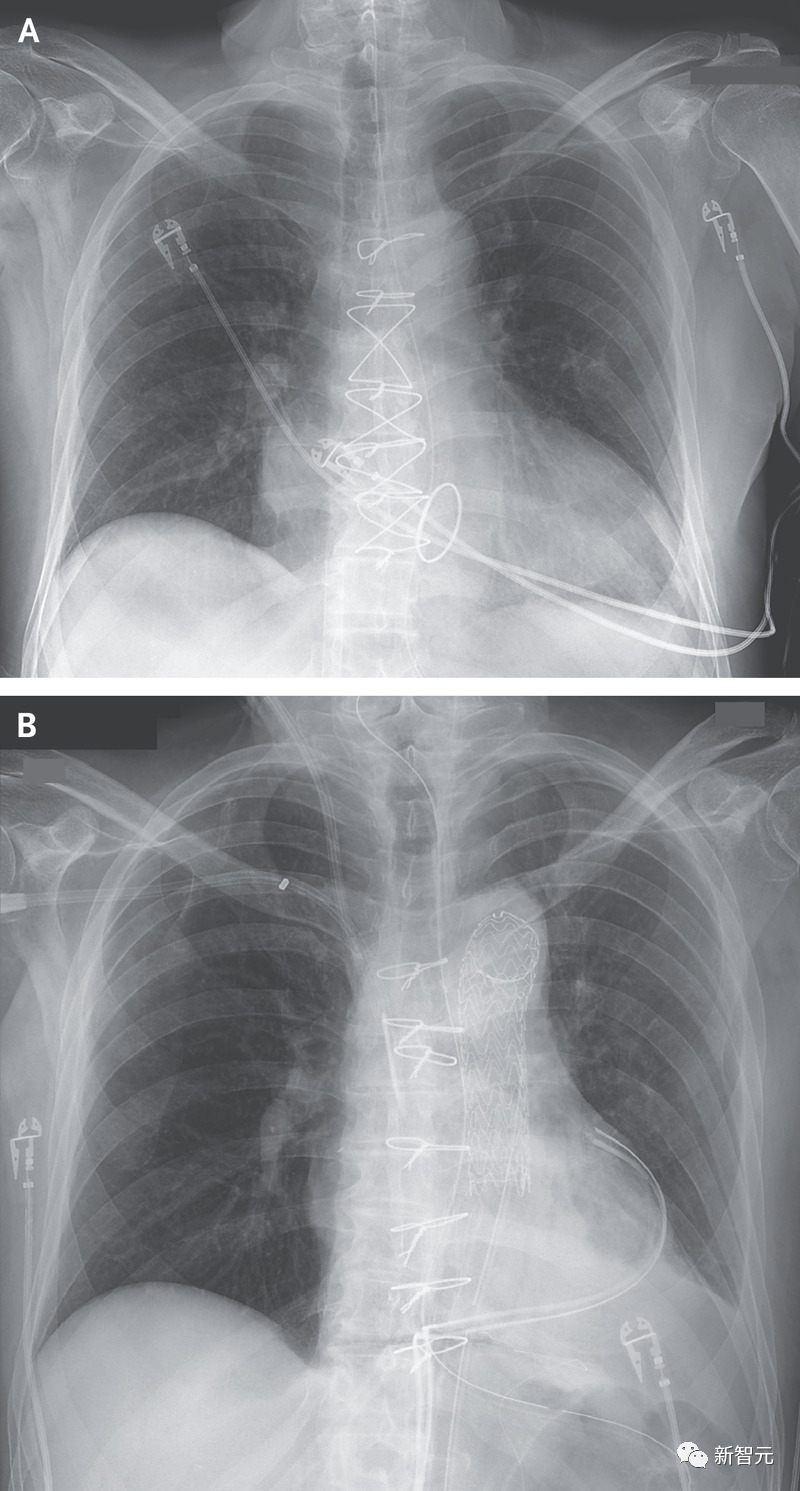

两次手术分别在今年的6月16号与7月6号在纽约大学的朗格尼蒂施医院进行,由纽约大学心脏移植外科主任Dr. Moazami操刀。

这两颗猪心的大小与人的大致相同,Moazami却发现在第一次移植中一些关键差异。

Kelly接受移植的供体猪有160磅(约73公斤)重,猪心脏要比一个重220磅(约100公斤)的人要小。

而且血管的大小和长度与Dr. Moazami在近1000例人与人之间移植手术中看到的不一样,因此对血管做出调整。

而第二例移植患者重130磅,猪心大小刚好合适。

因此,NYU团队仅用了3小时40分钟内完成了第二次移植,比第一次快了50分钟。

因此,术后医生对两位受试者进行了72小时的心脏功能监测。

在两个器官中均未观察到早期排斥的迹象,并且无需额外的机械或药物便能维持心脏功能。